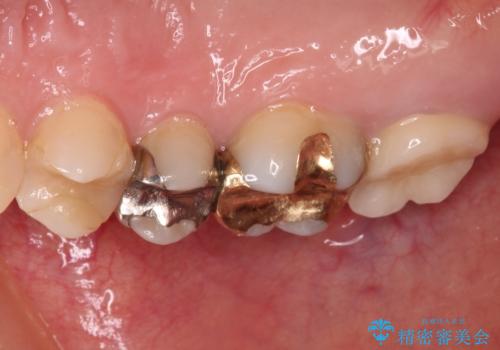

- 右上下の奥歯がむし歯でしみたり痛んだりするとのことで来院された患者様です。

下顎の奥歯は強い痛みを感じており、既に歯髄に不可逆的な炎症が起きていると診断されたため、根管治療の後にセラミッククラウンにて補綴治療を行うこととしました。

上顎の奥歯は最近銀歯による治療を行ったとのことでしたが、適合が不十分であり隙間からしみていたため、適合の良いゴールドインレーにて修復治療を行うこととしました。

下顎のむし歯は歯肉の中にまで及んでいたため、一部歯槽骨を削除し、歯肉縁上に健全歯質が位置するよう外科処置を併用しました。